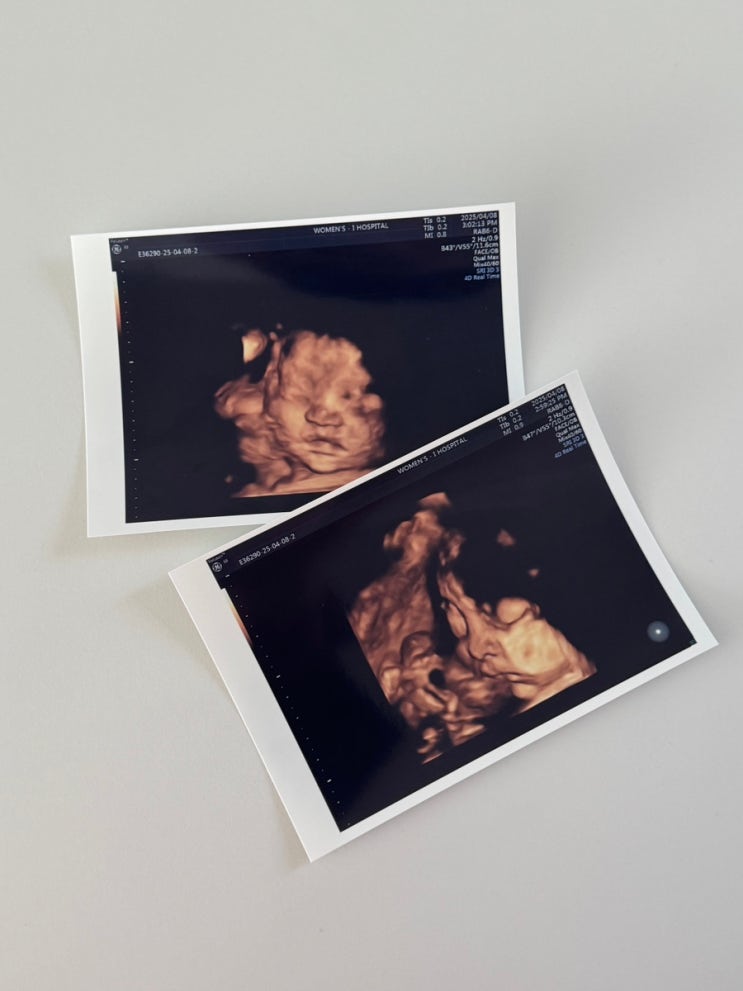

[임신 31주차] 조산위험 임산부 눕눕 생활 중

25.04.14 월요일인만큼 육아휴직급여문제도 해결하고 의료보험도 한번 더 확인하고 수유패드도 구매완료 했...